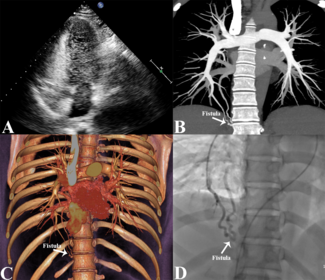

Zhenzhen Xiao, MD; Li Zhu, MD

A 51-year-old man presented with palpitations and shortness of breath for the past 4 years. Findings from electrocardiography and laboratory tests performed after physical examination were unremarkable.

12/23/2024

Journal of Invasive Cardiology